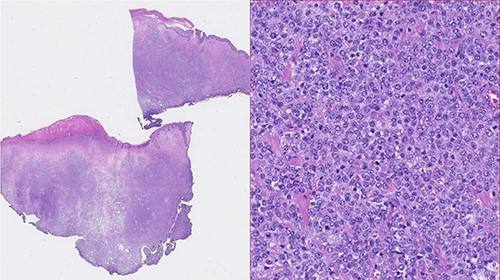

A 73-year-old Caucasian man with a history of hypertension, atrial flutter and Type 2 diabetes mellitus underwent left inguinal hernia repair by Rutkow-Robbins hernioplasty in 2017 without immediate surgical or postoperative complications. In 2021, he reports the appearance of a painless swelling in the left inguinal scar. The patient was medicated with antibiotics without improvement and was sent to the General Surgery consultation with the diagnosis of inguinal mesh rejection. Upon observation by General Surgery, the patient had an ulcerated area of the medial portion of the scar, measuring 1 × 2 cm, with drainage of seropurulent content and surrounding erythema, interpreted as the external orifice of a fistulous tract. The diagnosis of late mesh rejection was maintained, and the patient underwent prosthesis removal without hernia repair. During surgery, extensive peri-mesh fibrosis was found but without apparent signs of infection. The scar was removed en bloc including the ulcerated area and sent for anatomopathological examination. The surgery was uneventful and the patient was discharged. Histological examination (Figs 1–3) revealed extensive involvement of the dermis and hypodermis by a high-grade non-Hodgkin lymphoproliferative process with characteristics of diffuse large-cell B lymphoma, which focally conditions epidermal ulceration. The immunohistochemical study showed diffuse staining for CD20, MUM-1 and CD10, with weak and heterogeneous staining in ~40–50% of neoplastic cells for C-MYC and 80–90% of the same population cell for Ki-67. Immunostains for CD30 were not observed and with anti-CD3 and anti-CD5 antibodies, only marking of scattered rare reactive T lymphocytes was observed. Finally, the neoplastic cell population had no staining for bcl2, but diffuse staining for bcl6. Upon reassessment, the patient had wound dehiscence with an extensive ulcerated area (Fig. 4) and was oriented to hematology. Bone marrow biopsy, myelogram and flow cytometry were normal and computerized tomography of the neck, chest, abdomen and pelvis revealed a right inguinal adenopathy (Fig. 5). The patient was staged as IIa and proposed for systemic treatment with rituximab, cyclophosphamide, doxorubicin, vincristine and prednisolone (R-CHOP).

Photomicrographies. Left: Small magnification (HE) of a fragment of skin and subcutaneous tissue, with extensive epidermal ulceration and almost total occupation of the subcutaneous tissue by lymphoid tissue placed in a towel. Right: High magnification (HE ×40) with cytological detail of the lymphoid infiltrate, consisting of towels of voluminous cells with centroblastic morphology.